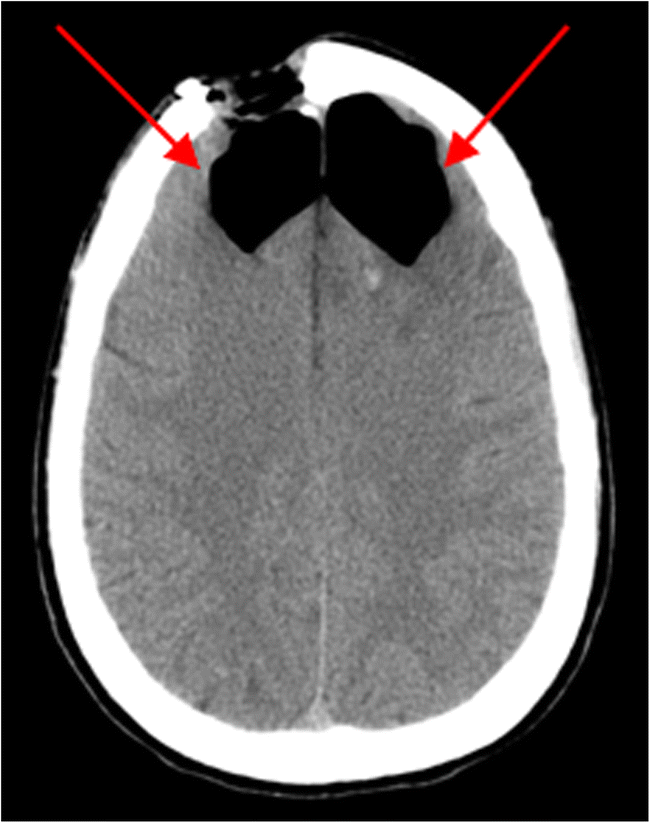

Tension Pneumocephalus With Mount Fuji Sign American Journal Of Neuroradiology

The Mount Fuji Sign Radiology

The Mount Fuji Sign Rcp Journals

The Mount Fuji Sign Nejm